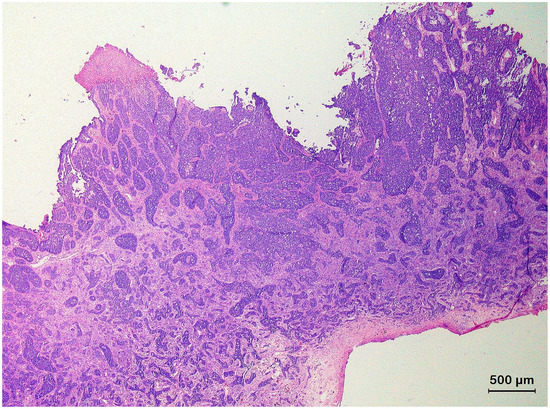

3.2. Squamous Cell Carcinoma and Its Histological Variants

3.3. Basal Cell Carcinoma and Its Histological Variants